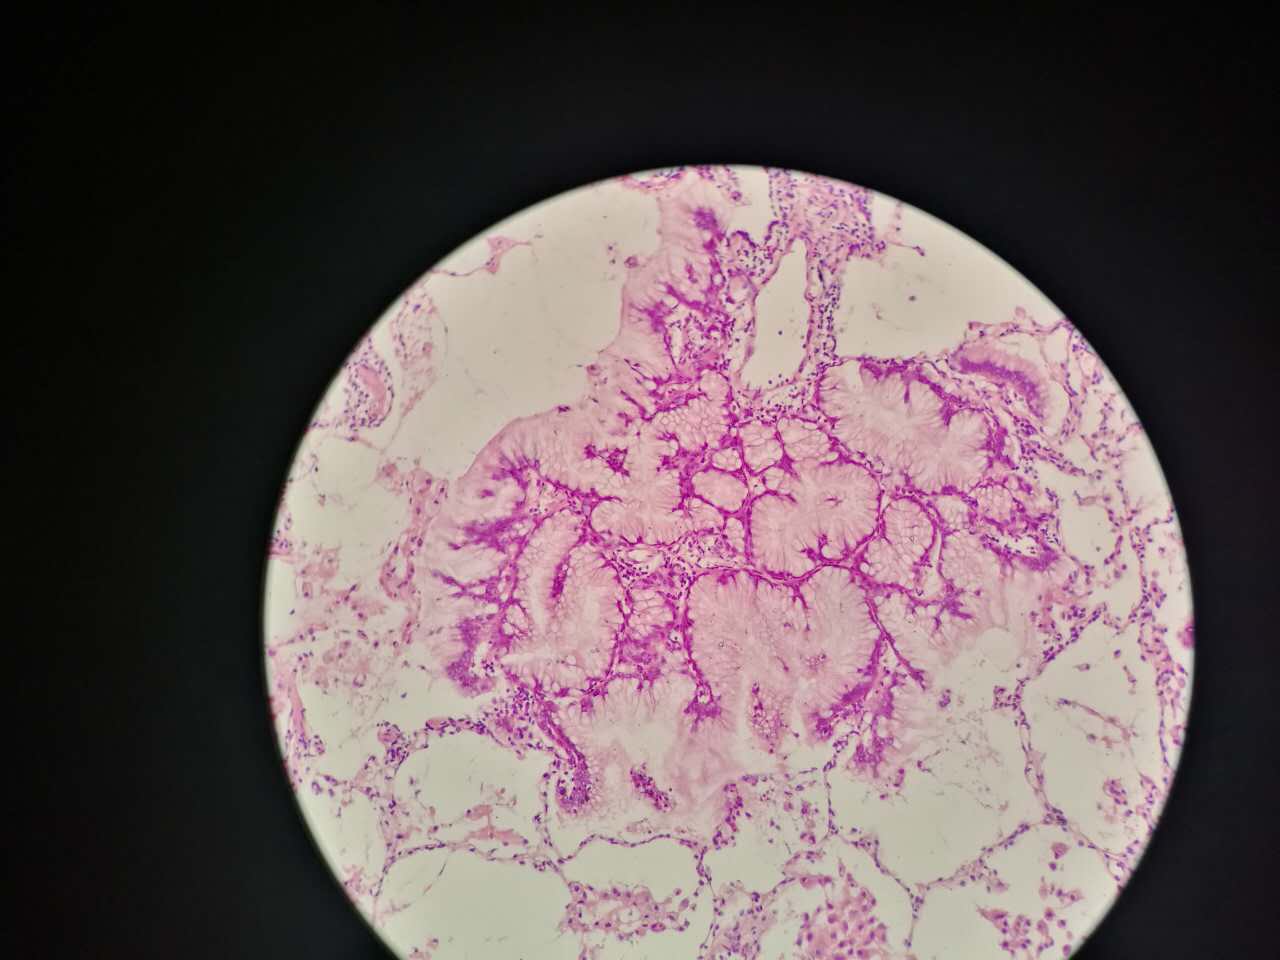

粘液型腺癌

粘液型腺癌是原发肺腺癌中的一种特殊类型

细胞内外含较多粘液

粘液型腺癌,细胞内粘液多,有点儿像支气管的粘液腺

细胞外粘液湖

粘液腺癌起源于细支气管和肺泡

这一幅的上方都是黏液湖

下方是正常肺泡

细胞内白颜色区是粘液,细胞外洋流样的也是粘液(湖)

黏液湖里可以飘着一些细胞,吞噬细胞及肿瘤细胞。

肿瘤细胞飘出去可以种植于肺泡上。

肿瘤细胞堆经常是离开的

中间这一团,整个都是飘过来种植长成这样

这在进展后期特别多见

早期飘散常很近